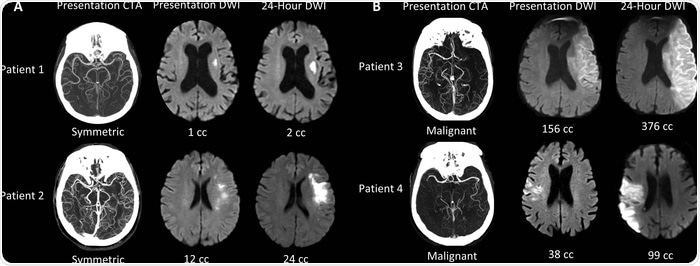

We are creating a machine learning algorithm that can identify LVO patients with symmetric collateral circulation that is a marker of small cores that are growing slowly. This is one of several algorithms that we are combining into a suite of algorithms that are capable of capturing all of the key information for the evaluation of the acute stroke patient.